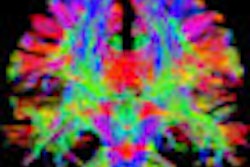

A multiparametric approach promises improved detection and characterization of prostate cancer. He thinks the way forward is T2-weighted diffusion and dynamic imaging. Future perspectives in prostate cancer imaging look set to be interesting, and he welcomes the day when all patients will have an MRI examination before they have a biopsy. Contrast agents such as iron oxide particles (small nanoparticles that travel to the lymph nodes) promise to assist in the detection of small (2 mm) lymph nodes. Barentsz hopes for more precise diagnosis of prostate cancer, which he believes will be achieved with the use of MR-ultrasound fusion and minimally invasive therapy by treating localized tumors with high-intensity focused ultrasound under MR guidance.